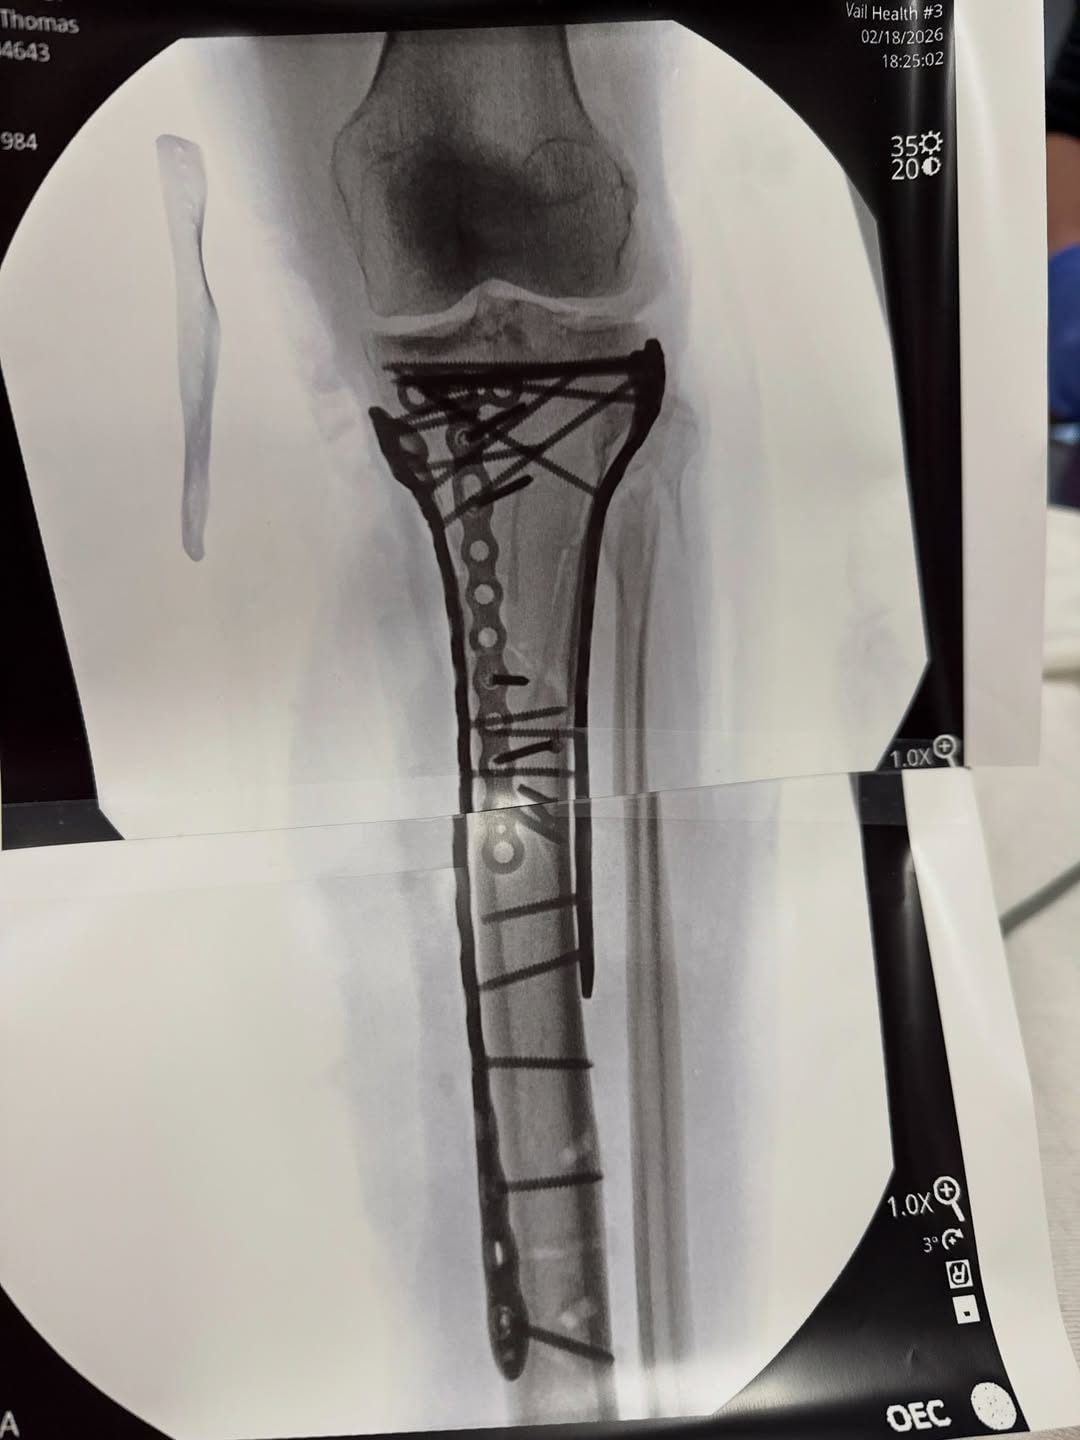

Lindsey Vonn e l'ultima operazione: "Più di 6 ore, un sacco di piatti e viti per rimetterla insieme"

"Ho superato l'operazione chirurgica, ci sono volute un po' più di 6 ore per completarla – ha scritto la Vonn nel post – Come potete vedere, ha richiesto un sacco di piatti e viti per rimetterla insieme, ma il dottor Hackett ha fatto un lavoro incredibile. Con l'entità del trauma, ho avuto un po' di difficoltà nel post operatorio e non sono ancora riuscita ad essere dimessa dall'ospedale. Ci siamo quasi. Piccoli passi. Presto spiegherò l'infortunio e cosa significa tutto questo".

La radiografia della gamba sinistra della Vonn: una quantità impressionante di metallo

Da quello che si vede nella radiografia, la stabilizzazione della frattura complessa della tibia ha richiesto una grossa placca lungo l'asse dell'osso (che appare fratturato in più pezzi) e tantissime viti che la fissano in vari punti, oltre a un fissatore esterno con barre, anelli e perni che escono dalla pelle. Ora l'attenzione dei medici sarà sulla gestione del dolore, l'evitare infezioni e una riabilitazione che si annuncia lenta e difficile.